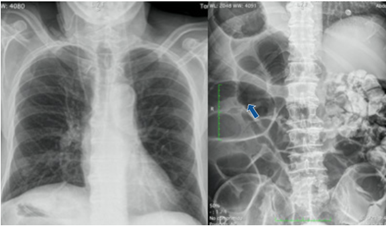

Se trata de un varón de 72 años, con antecedente de prostatectomía radical en 2019 por carcinoma de próstata, complicada con perforación iatrogénica de recto que requirió colostomía, con posterior reconstrucción del tránsito en un segundo tiempo quirúrgico. Se encontraba recibiendo radioterapia por recaída, cuando acude a urgencias por presentar dolor abdominal intenso, localizado en fosa iliaca derecha, asociado a cese de expulsión de heces y gases. Durante el examen físico al momento del ingreso el paciente se encontraba hemodinámicamente normal y estable, afebril, con abdomen distendido y timpánico, doloroso a la palpación profunda en hemiabdomen derecho. En el tacto rectal presentaba la ampolla rectal vacía. Se completó el estudio mediante analítica e imágenes diagnósticas, a saber: radiografía de tórax, que mostró ubicación cardíaca habitual con una discreta cardiomegalia, radiografía de abdomen, en la que se observaba marcada dilatación del marco cólico con ausencia de gas en ampolla rectal en relación con obstrucción intestinal (Figura 1), y tomografía (TC) abdominal, donde se informó situs inversus, marcada dilatación de ciego en hipocondrio derecho, con ingurgitación de vasos y signo del remolino, acompañado de hallazgos sugestivos de un patrón de oclusión a nivel de íleon distal, junto con líquido libre de localización perihepática, periesplénica y pélvica (Figura 2).

Figura 1. Radiografía de tórax (izquierda) donde se aprecia la ubicación cardíaca habitual. Radiografía de abdomen (derecha) con marcada dilatación de marco cólico (flecha) y ausencia de gas en ampolla rectal.